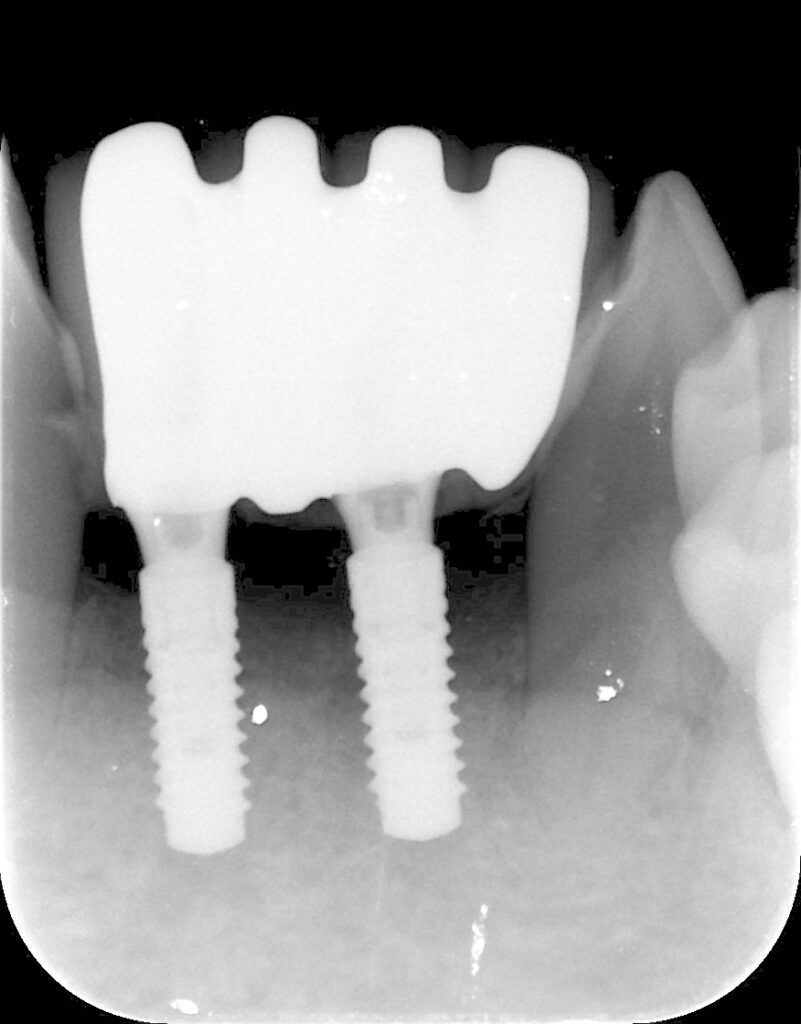

下顎前歯部インプラント 2026 3/09 臨床アラカルト 2026年2月17日2026年3月9日 歯周病で下顎の前歯を4本失った方です。最終的にこんな形で修復しました。 臨床アラカルト よかったらシェアしてね! URLをコピーしました! URLをコピーしました! 矯正実習セミナーに参加してきました。 博多歯周外科実習セミナー 関連記事 学んだばかりの技術を活かす(歯周組織再生療法) 2026年5月11日 患者さんから学ぶ 2026年4月20日 80歳の方の矯正 2026年3月24日 学んだ事を早速応用しました 2026年3月10日 トラブルシューティング 2026年2月4日 80歳で矯正を希望された方 2025年12月26日 貼物作り 2025年11月27日 歯科は考古学? 2025年11月6日 コメント コメントする コメントをキャンセルコメント ※ 名前 ※ メール ※ サイト 次回のコメントで使用するためブラウザーに自分の名前、メールアドレス、サイトを保存する。 上に表示された文字を入力してください。